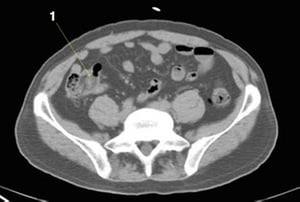

CT-Scan von Abdomen und Becken mit normaler Anatomie ohne Kontrastmittel (Folie 22)

1 = M. iliaca.

© Springer Science+Business Media